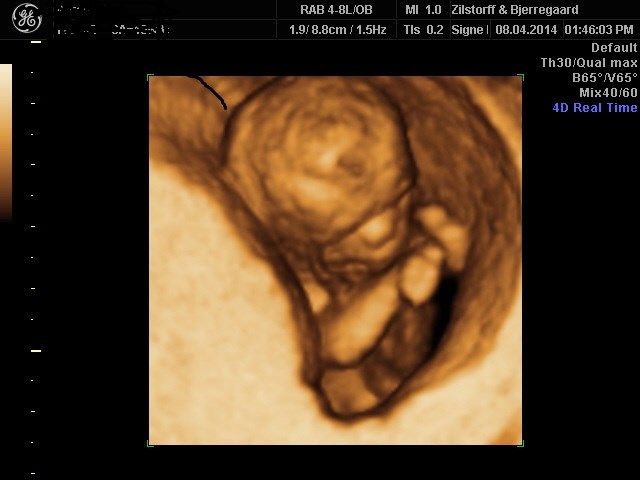

Og i skal ikke snydes for et lille billede, selvom det ser lidt uhyggeligt ud